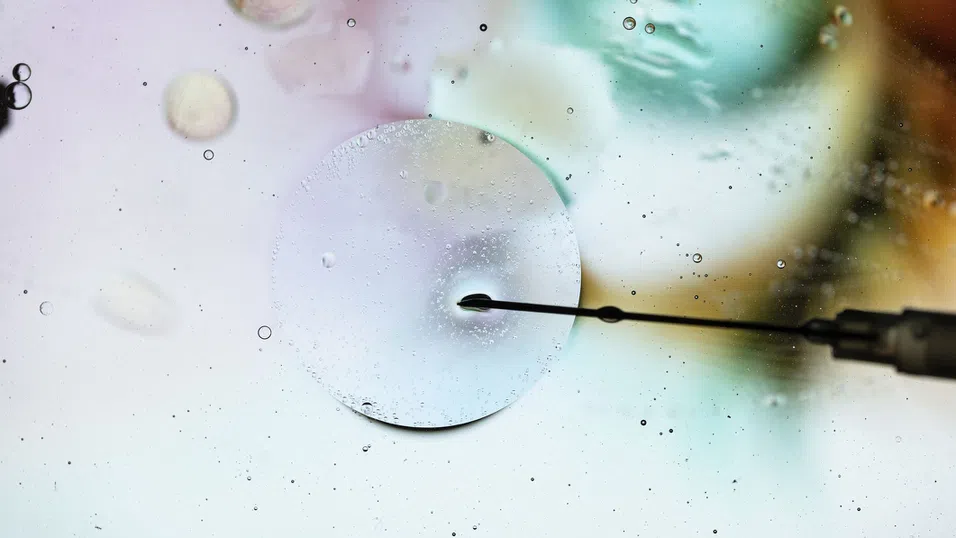

Революционното изследване предполага, че възрастово обусловен дефект, който причинява генетични грешки в ембрионите, може да бъде обърнат чрез добавяне на ключов протеин към яйцеклетките. Когато яйцеклетки, дарени от пациентки в клиники по репродуктивна медицина, са получили микроинжекции с този протеин, вероятността да проявят дефекта е била почти наполовина по-ниска в сравнение с нелекуваните яйцеклетки.

По-ранни изследвания на Шух и екипа ѝ показват, че протеинът Shugoshin 1, който действа като своеобразно „лепило“ за хромозомните двойки, намалява с възрастта. В последните експерименти с яйцеклетки от мишки и хора учените установяват, че микроинжектирането на Shugoshin 1 изглежда обръща проблема с преждевременното разделяне на хромозомите.

Използвайки яйцеклетки, дарени от пациентки в клиниката по фертилитет Bourn Hall в Кеймбридж, екипът установява, че делът на яйцеклетките с дефекта спада от 53% при контролната група до 29% при третираните яйцеклетки. При жените над 35-годишна възраст се наблюдава подобна положителна тенденция, като дефектите намаляват от 65% на 44%. Макар този резултат да изглежда впечатляващ, изследователите уточняват, че той все още не е „статистически значим“. Причината за това е малкият брой изследвани проби в тази специфична група – лекувани са били само девет яйцеклетки, което е недостатъчно за окончателни научни изводи.

Освен интрацитоплазменото инжектиране на сперматозоид (ICSI), към момента няма други утвърдени терапии, включващи микроинжекции директно в яйцеклетки. Екипът обаче не очаква проблеми със сигурността и вече води разговори с регулаторните органи за провеждане на клинично изпитване. Ключов въпрос ще бъде дали отчетеното подобрение в качеството на яйцеклетките води и до ембриони с по-малко генетични грешки.